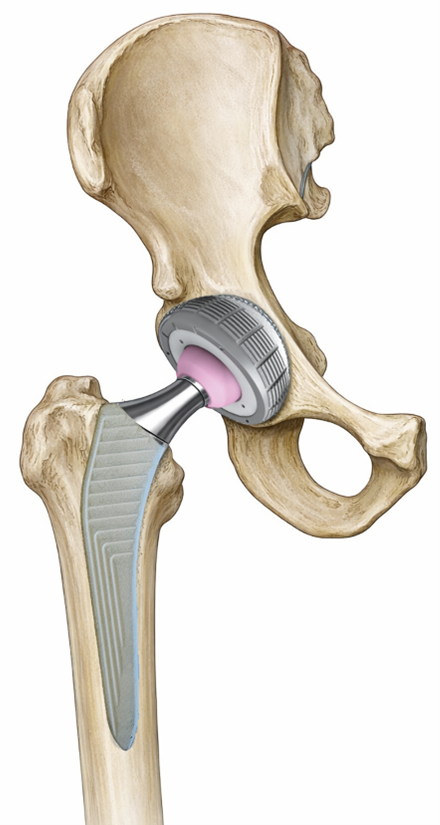

Une PTH remplace les surfaces articulaires usées :

- Cupule + insert côté bassin.

- Tige + tête côté fémur.

Comment la prothèse tient-elle dans l’os ?

Deux modes de fixation :

- Cimenté (PMMA médical), donnant une tenue immédiate dès la fin de l’opération.

- Non cimenté, avec une surface poreuse ostéochonductrice (titane poreux ou titane recouvert d’hydroxyapatite) qui permet à l’os de s’intégrer progressivement à la surface de la prothèse. Pendant les deux à trois premiers mois après l’implantation de la prothèse, avant le collage biologique de l’os à la prothèse, la tenue est assurée par la pression qu’exerce l’os sur la tige et la cupule, à la manière d’un clou planté dans du bois.